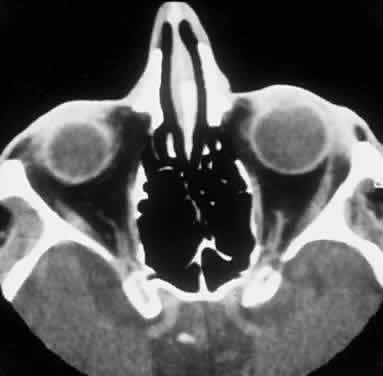

Multiple myeloma is the prototypic systemic plasma cell tumor that occurs in the elderly, more commonly men, with multiple masses of plasma cells disseminated throughout the skeletal system and soft tissue.7 Extraskeletal metastases occur in 70% of cases, either by hematogenous spread or by direct extension. Morbidity and mortality stem from bone marrow invasion with resultant anemia, infiltration of visceral organs, amyloid deposition, and secretion of immunoglobulin and osteoclast-activation factors. Multiple myeloma can metastasize to the kidney, adrenal gland, heart, and liver and can cause punched-out lesions of the skull and vertebral fractures. Mean survival is 3 years with chemotherapy, and the presence of Bence Jones proteins worsens prognosis. An aggressive variant of multiple myeloma is disseminated nonosteolytic myelomatosis, which progresses rapidly, involving bone marrow and soft tissues without radiographic changes. Orbital soft tissue metastasis with orbital bone destruction has been noted in a series to occur in 5 in 2000 cases, and invasion of orbital bone is even less common94–98 (Fig. 15). Amyloid deposition into the extraocular muscles can occur.99

Fig. 15. A 48-year-old Indian man with known systemic multiple myeloma and subsequent plasmacytoma involving the left orbit with lateral orbital wall destruction (A), as evident on axial CT scan (B).